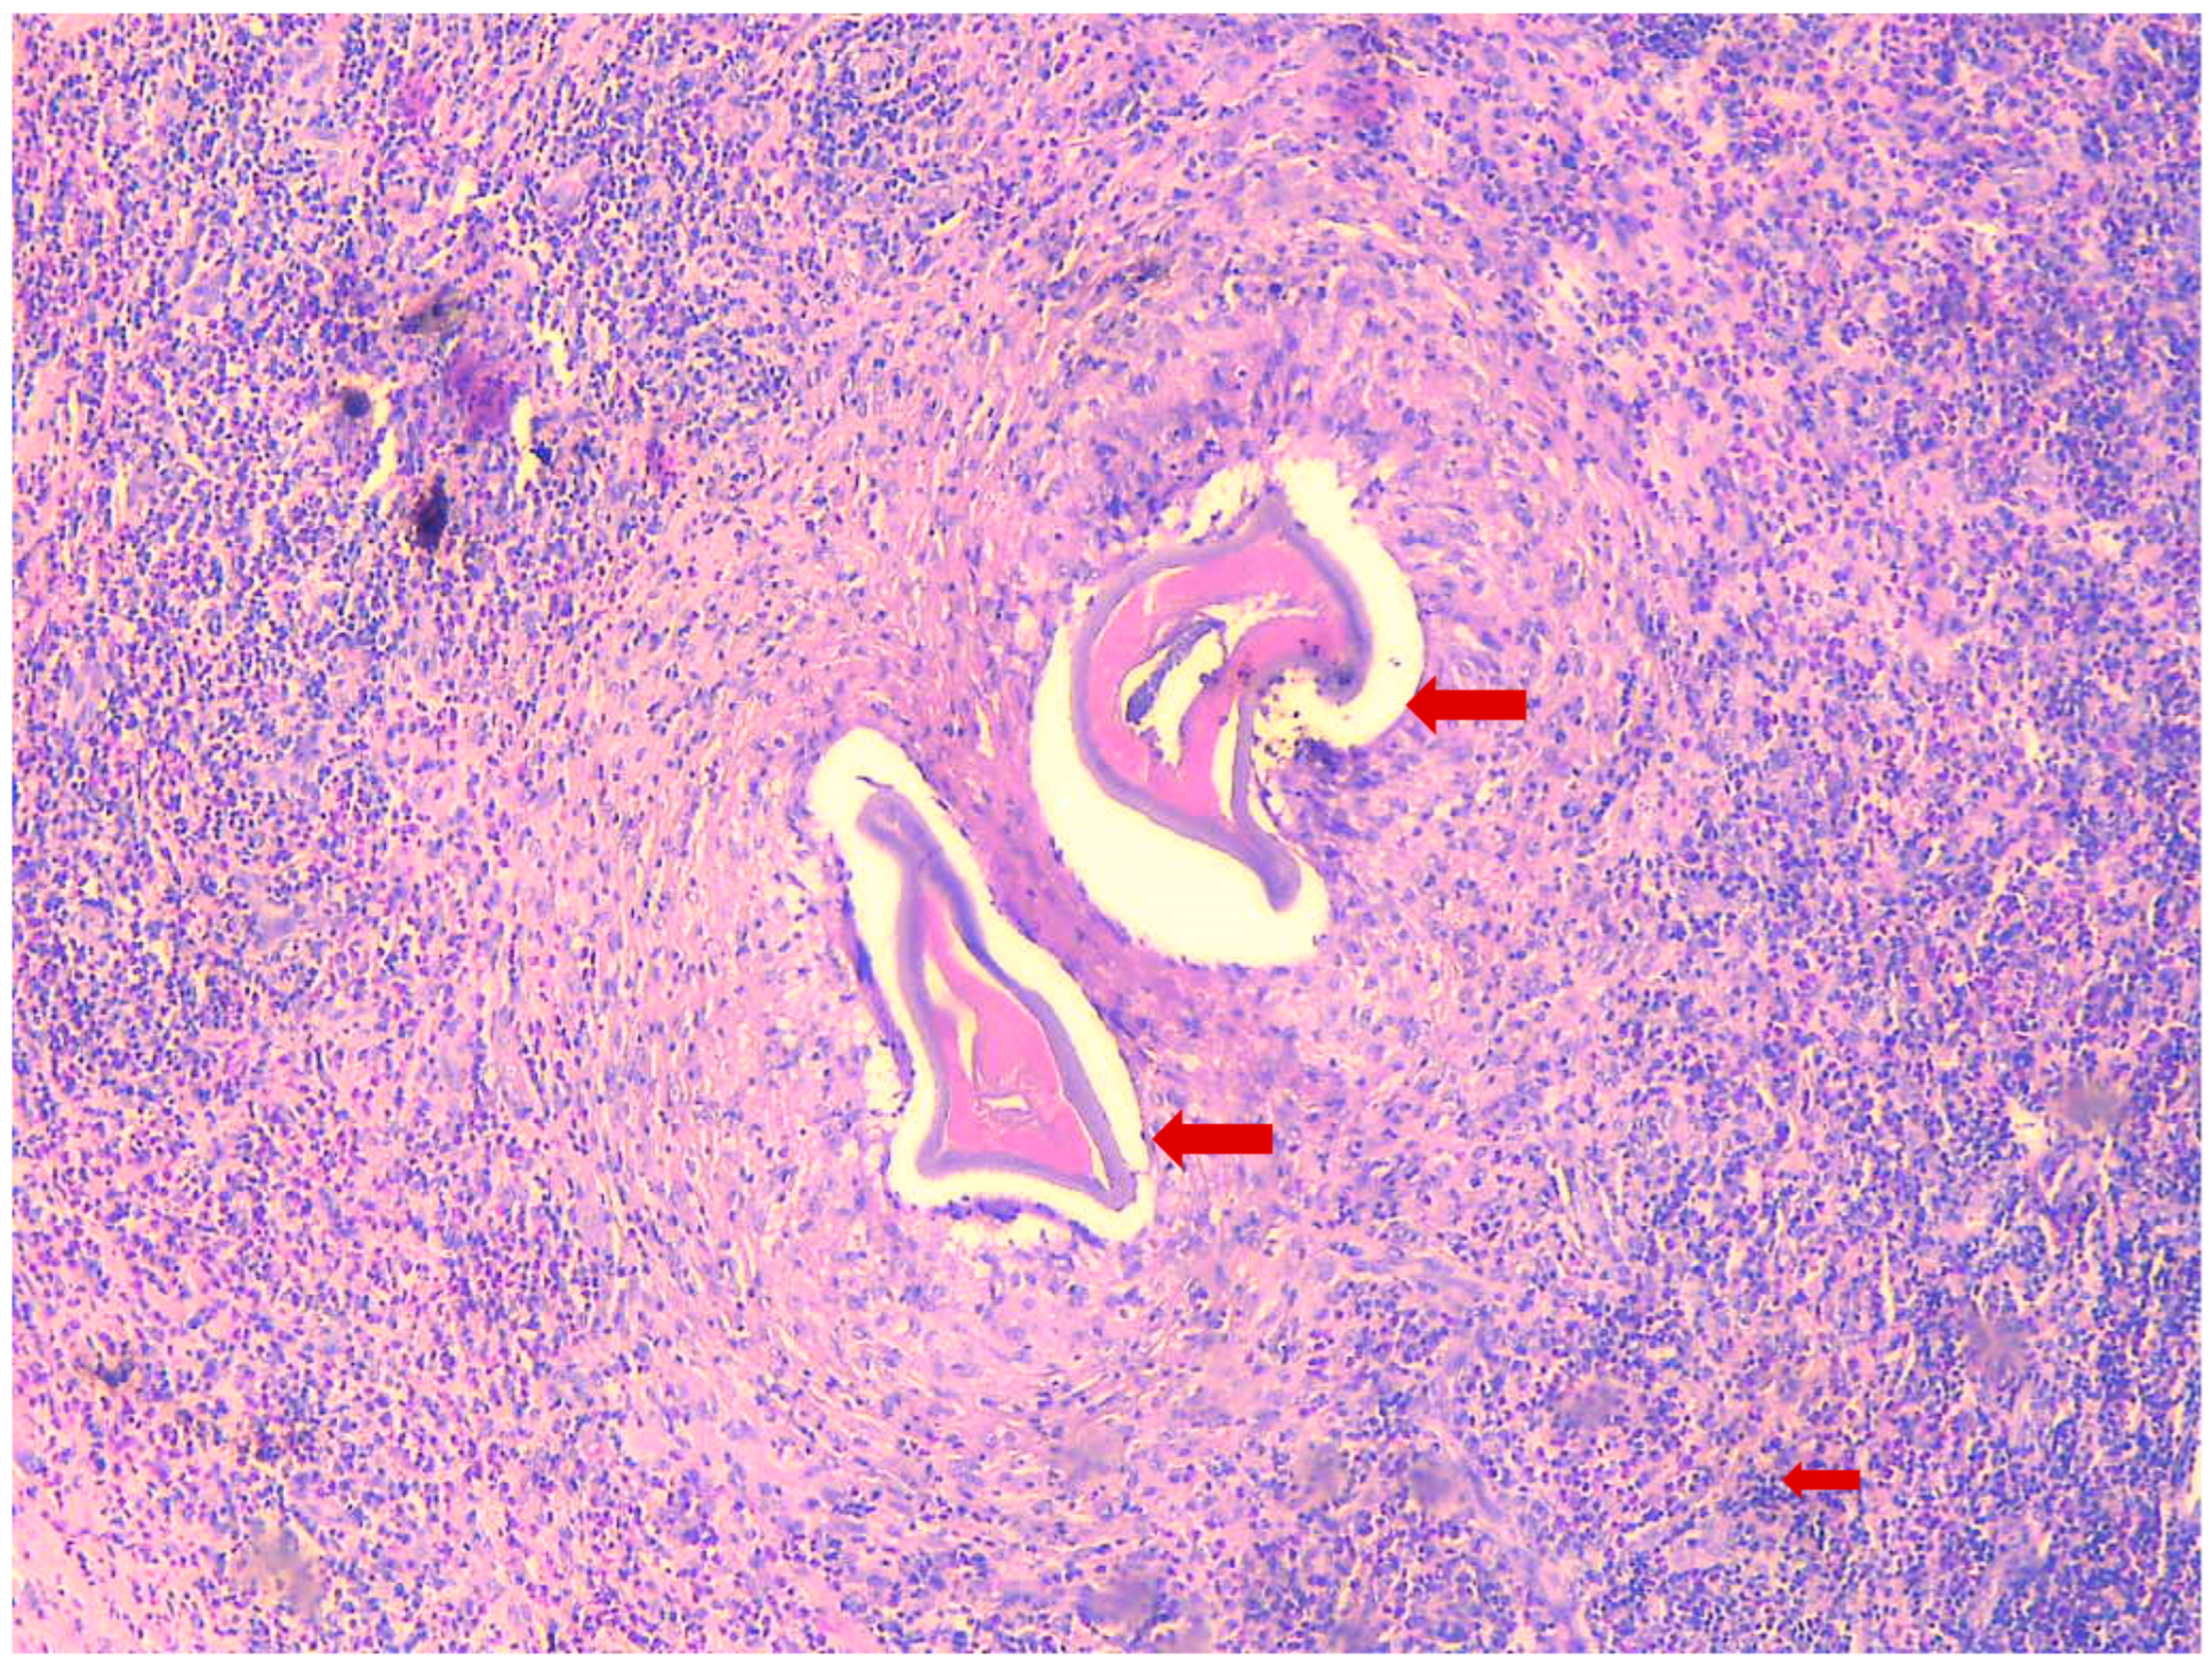

Figure 2.

Histopathological section of the biopsy, H&E staining, 20×, a histopathologic section of the biopsy with a granuloma and cross sections of dirofilarial; Small arrow shows the inflammatory infiltrate with lymphocytes and eosinophils; Large arrows show cross sections of the worm.